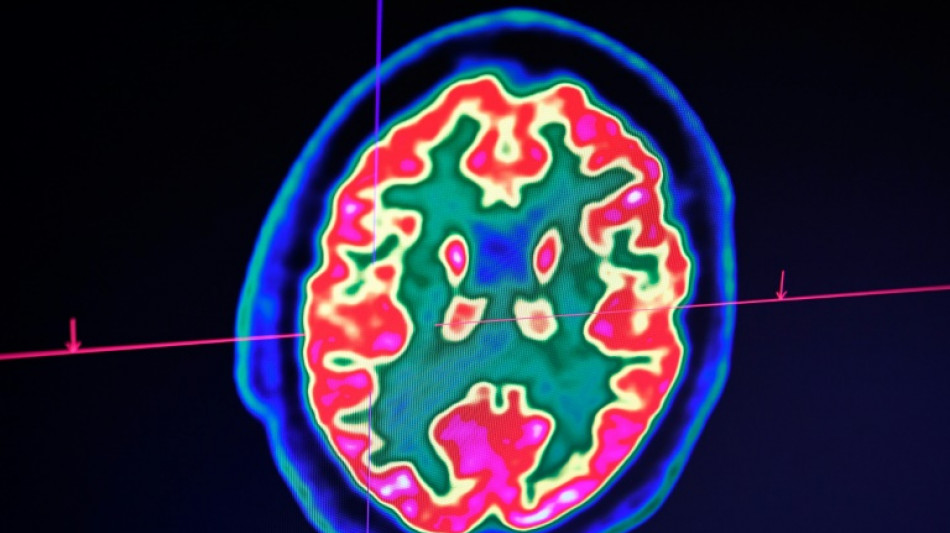

Sclérose en plaques: la découverte d'un lien avec un virus fait espérer une meilleure riposte / Photo: Fred TANNEAU - AFP/Archives

Celle-ci est une maladie auto-immune du système nerveux central (cerveau et moelle épinière). Elle provoque un dérèglement du système immunitaire, qui s'attaque à la myéline, la gaine protectrice des fibres nerveuses.